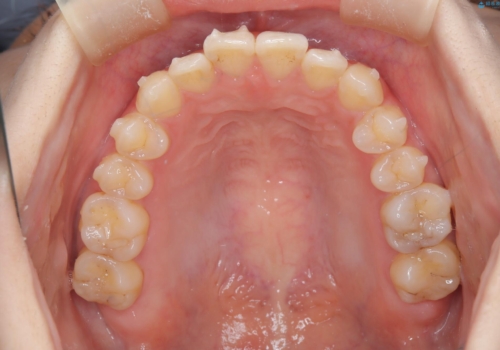

- 治療計画